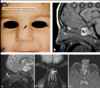

Buphthalmos

Buphthalmos: